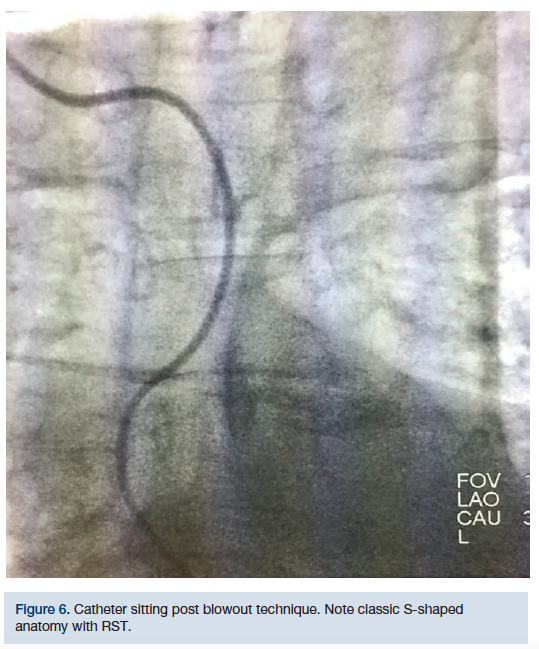

This technique was initially used on a 68-year-old female, diabetic, 5 feet, 4 inches tall, hypertensive, with severe RST (Figures 5-8). Despite several different catheter positions, wires, and extensive deep inspirations, the wire was repeatedly biased towards the descending aorta. Prior to bailing out to an alternative approach, we hypothesized that doing the exact opposite might gain us access to the AA. After several minutes of fluoroscopy and extensive deep inspirations disallowed navigation, a single deep expiration allowed our wire and catheter access into the AA with minimal fluoroscopy.

Upon catheters being placed at the origin of the brachiocephalic trunk or the transverse aorta, the patient is asked to take a deep breath in and “blow” it all out. At that moment, the operator will advance the guidewire in an effort to access the AA. Logic dictates that if a deep inspiration straightens RST for catheter navigation, then a deep expiration would amplify tortuosity, disallowing catheter navigation. While inspiration distends out RST, it also creates a rigid pathway for catheters (Figure 9).

While distended, it is possible this pathway may bias catheters towards the descending aorta. However, a deep expiration “softens” the anatomy, to a small degree, increases the lumen size, and may improve the entry angle into the AA. This may allow a wire to pass into the AA with relative ease. This technique has worked several times on patients that have had severe RST. The “blowout” technique can be attempted when conventional methods of accessing the AA fail and/or when deep inspiration continuously biases catheters towards the descending aorta.